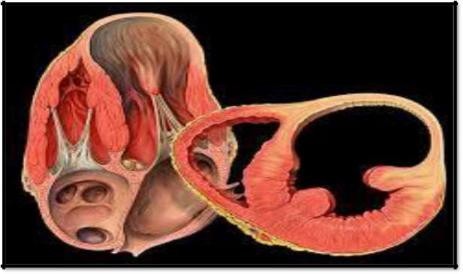

This condition is where the valves in your heart that control the free flow of blood are not working properly. The valves of the heart ensure that your blood freely flows in a forward direction and cannot leak backward. The way in which a healthy heart operates is the same for everyone.

The heart contains four chambers with the heart valves placed at the exit of each chamber. The blood flows through both your right and left atria into the ventricles through the mitral and tricuspid valves. When your ventricle chambers are full, the valves will shut, stopping the blood from returning to the atria when the ventricles contract. When the ventricles start to contract, the aortic and pulmonic valves are forced to open. The blood from the left ventricle goes into the aorta and then to the rest of the body after passing through the aortic valve. The blood from the right ventricle goes into the pulmonary artery through the pulmonic valve.

Once the ventricles are done contracting and begin to relax, both the valves are shut. This prevents any blood from flowing back. This process repeats itself throughout an entire lifetime. There are two main types of heart valve disease.

Valvular stenosis occurs when one or more valves are narrowed, stiffened, thickened or blocked. It can lead to the heart pump insufficiency, and there'll be a lack of blood on different body parts. All four of the heart valves can develop stenosis.

The other common type is valvular insufficiency. This happens when a heart valve does not seal or close properly, allowing some blood to be forced or leak back into the chamber. If this condition worsens, it forces the heart to work harder to supply the needed blood to the body.